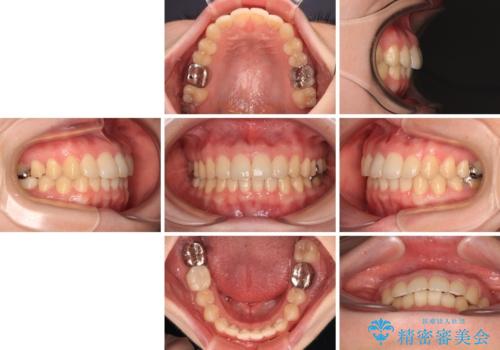

デコボコ歯列をきれいに インビザラインによる矯正治療

- 上下歯列全体のデコボコを気にして来院された患者様です。

主に下顎歯列全体の後方移動とIPR(歯と歯の間を削る)によってデコボコが解消するように設計し、インビザラインにより治療を行うこととしました。

1年半程度で終了するのではないかと予想しましたが、途中1年以上の来院がなく、トータルで3年の時間がかかってしまいました。

前歯のデコボコはより改善することが望ましい状態でしたが、患者様の希望により終了することとなりました。